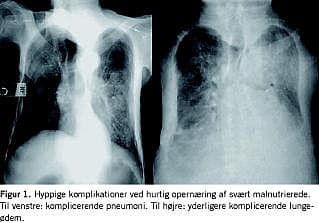

Efter initial rehydrering og behandling af patientens infektion blev der påbegyndt opernæring med sondemad, nutrison standard, men grundet kvalme og utilpashed blev det vurderet, at sondemaden ikke blev optaget, og der blev skiftet til peptisorb, der indeholder mellemkædede triglycerider (MCT)-fedt og spaltede peptider. Initialt blev der givet 25 kCal/kg. Dette medførte også uacceptable bivirkninger, og der blev skiftet til en kombination af peptisorb i lavere dosering og parenteral ernæring. Patienten fik fra starten tilført thiamin og øvrige B-vitaminer. Efterhånden som vi fik biokemiske mål for, at patienten også manglede D-vitamin, A-vitamin, K-vitamin, zink og jern, blev der substitueret for disse mangler. I de følgende to måneder var forløbet præget af tilbøjelighed til lungeødem som udtryk for kardiovaskulært svigt og recidiverende infektioner (Figur 1 ) med fornyet vægttab til følge. Patienten fik konstateret truende corneaperforation som følge af ekstremt udtyndede corneae og lagoftalmus.